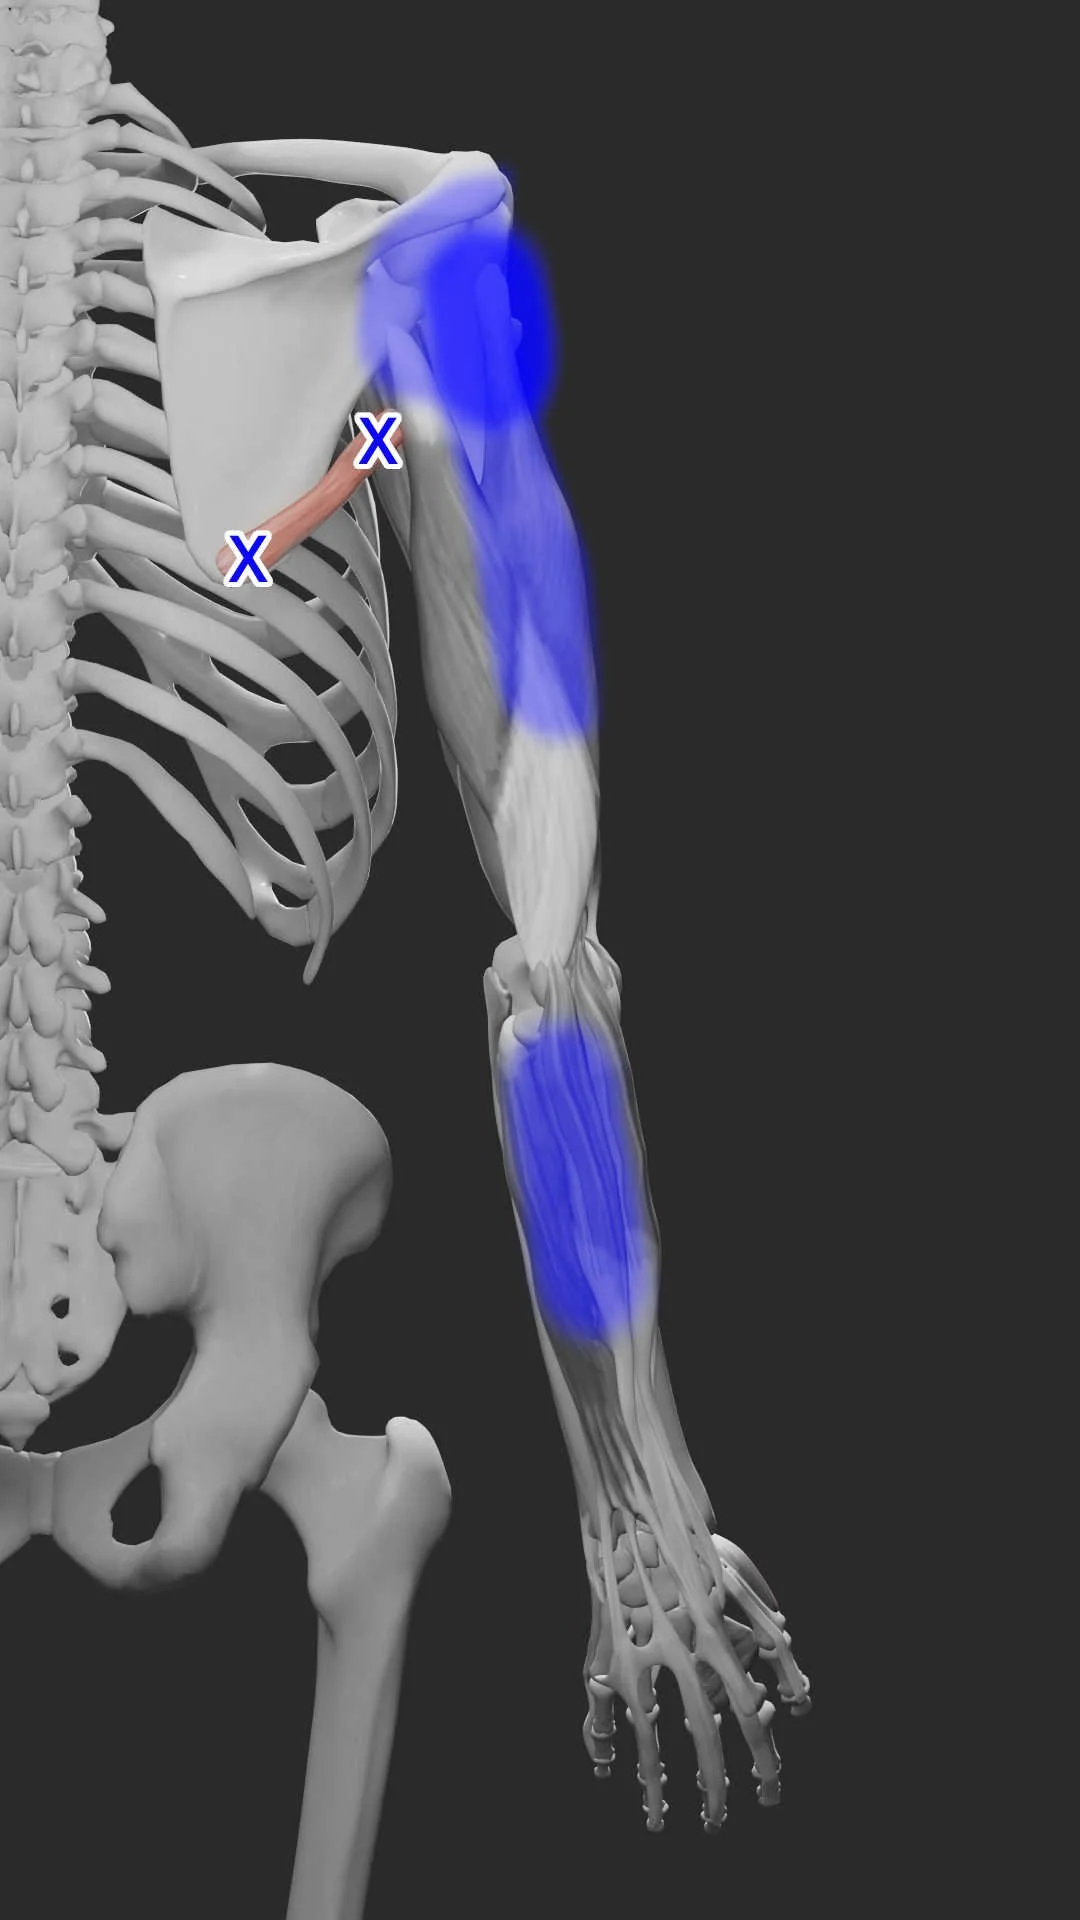

What is Pectoralis Minor Syndrome?

Discover the causes, symptoms, and effective non-surgical treatments for Pectoralis Minor Syndrome, a hidden source of shoulder and arm pain, including acupuncture and dry needling.